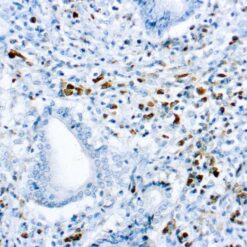

Leukocyte Common Antigen (LCA)/CD45

CD45R, also designated CD45 and PTPRC, has been identified as a transmembrane glycoprotein, broadly expressed among hematopoietic cells. Multiple isoforms of CD45R are distributed throughout the immune system according to cell type. These isoforms arise because of alternative splicing of exons 4, 5, and 6. The corresponding protein domains are characterized by the binding of monoclonal antibodies specific for CD45RA (exon 4), CD45RB (exon 5), CD45RC (exon 6) and CD45RO (exons 4 to 6 spliced out). The variation in these isoforms is localized to the extracellular domain of CD45R, while the intracellular domain is conserved. CD45R functions as a phosphor-tyrosine phosphatase. Antibody to CD45 is useful in differential diagnosis of lymphoid tumors from non-hematopoietic undifferentiated neoplasms.

| Positive Control Tissue | Tonsil |